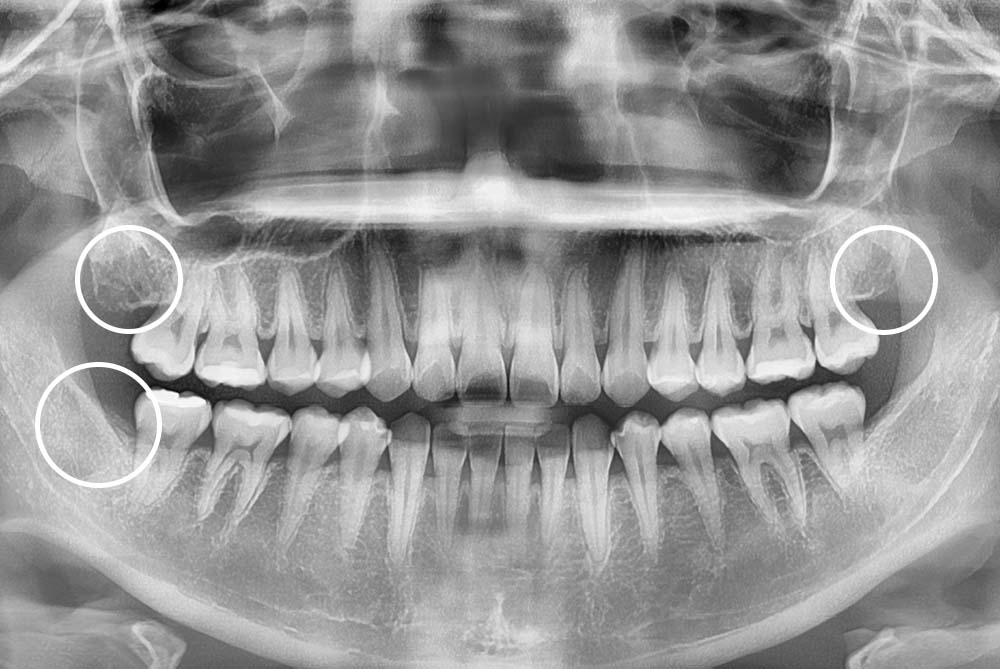

[사랑니] 매복 사랑니 발치

치료전 : 2018-03-22

치료후 : 2022-03-12

세종치과는 구강악안면외과학 박사이신 원장님이 발치하는 치과입니다.